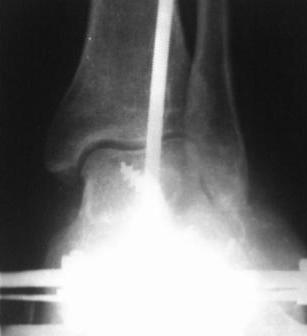

Больной 1964 г.р. С 30.08-по 14.09.07г. лечился в г. Иркутске, в МУЗ Медсанчасть ИАПО с д-зом - Кататравма. З/осколчатый в/с перелом обеих пяточных костей со смещением. З/компр, перелом тела L-2 п-ка 2-степ, неосложненный. Произведено скелетное вытяжение по Каплану, но больной до конца не лечился, от операции отказался, наложена гипсовая лонгетная повязка и выписан.( из выписки и/б ) К нам обратился с жалобами на деформации стопы, боли при ходьбе. Ходит при помощи костылей. Наш план, учитывая наличие подтаранного артроза с болевым синдромом - подтаранный и пяточно-кубовидный артродез с коррекцией варусной деформации.Уважаемые коллеги, помогите советом

Уважаемые коллеги, всем большое спасибо!!!

28.02.08г. произведен трехсуставной артродез таранно-пяточного, таранно-ладьевидного и пяточно-кубовидного суставов, с клиновидной остеотомией пяточной кости, с заполнением синуса костными осколками. Фиксация таранно-пяточный стягивающим винтом, таранно-ладьевидный и пяточно-кубовидный спицами, варусная деформация стопы устранена. Для наблюдения за состоянием раны и стопы а также для фиксации и поддержания напряжения произведен к/остеосинтез аппаратом Илизарова.

Почему не сделал чисто подтаранный артродез? Потому что и так нарушена биомеханика стопы, после подтаранного артродеза еще больше нарушается, особенно в суставе Шопара, поэтому артродезировал и его.